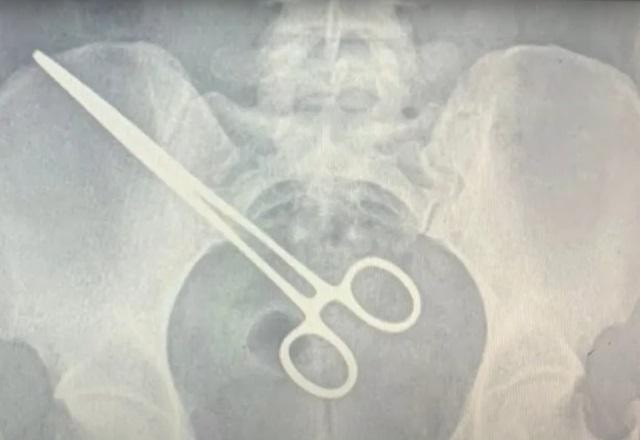

A imagem do raio-x mostra a pinça cirúrgica alojada no corpo da paciente. Com o objeto esquecido, uma nova cirurgia foi feita para a retirada do item, além de dez centímetros do intestino, ferido pela pinça. Por conta do erro médico, Jade procurou um advogado e pretende entrar com uma ação na Justiça.